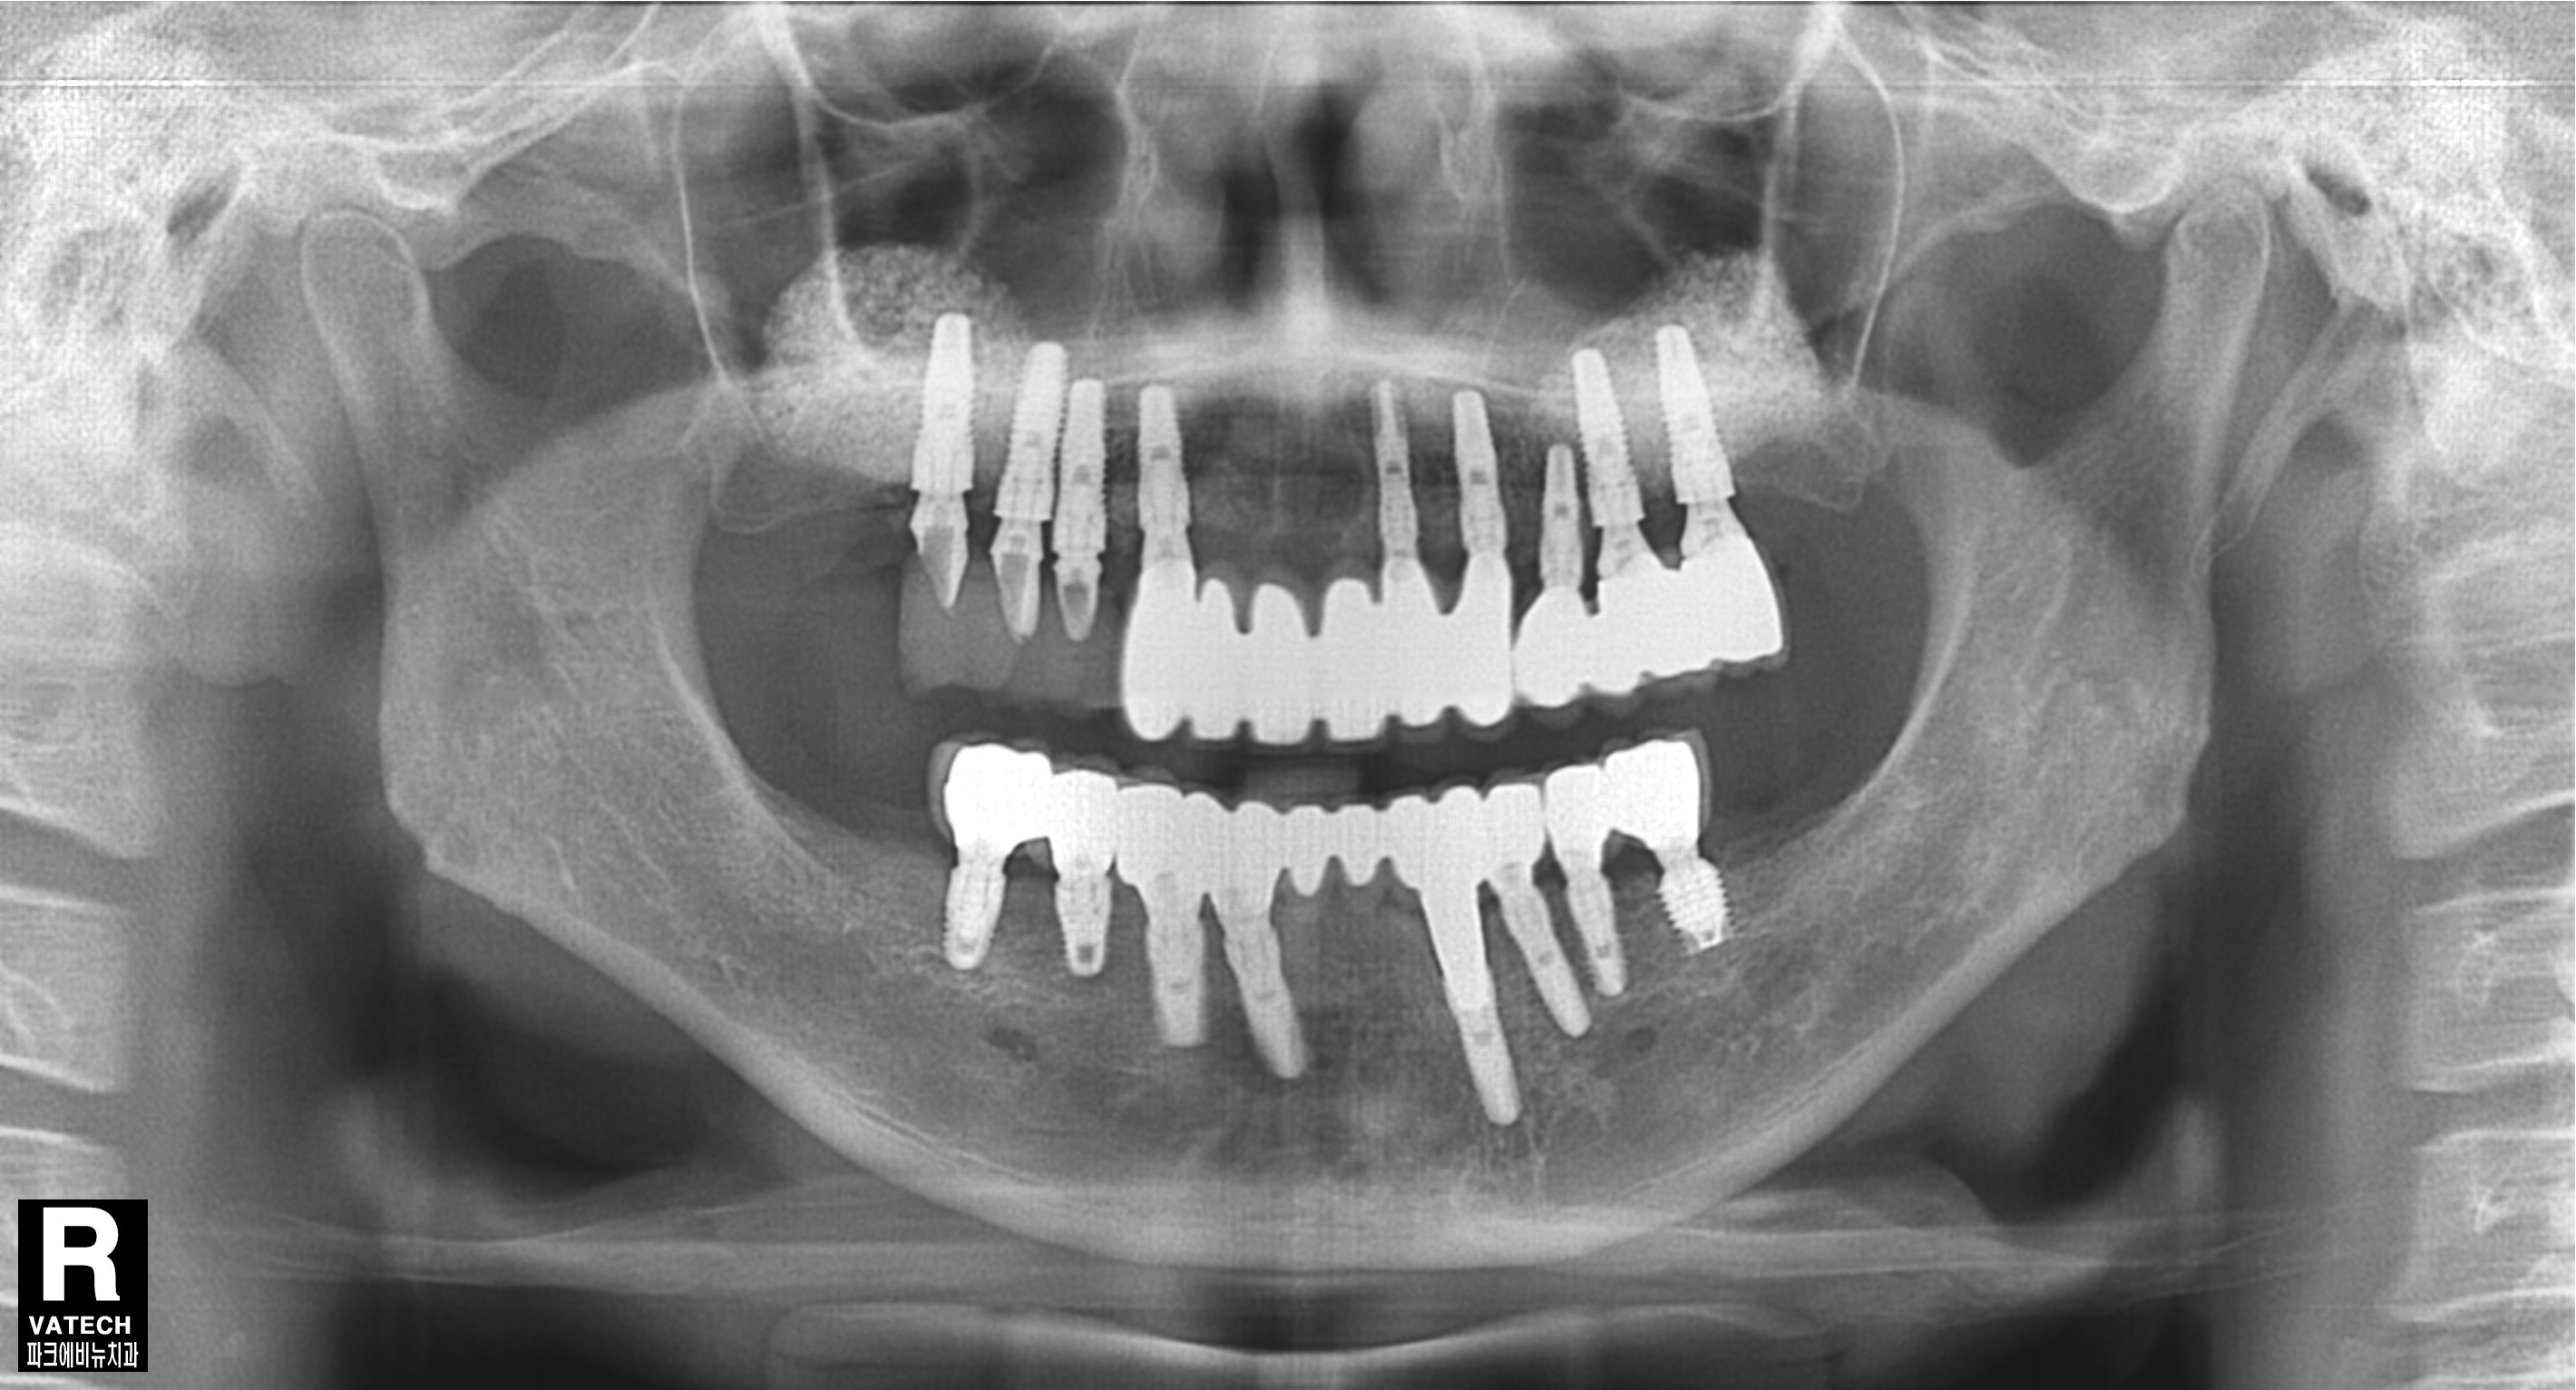

파노라마 방사선 사진도 살펴보면 치아를 잡는 치조골이 치아 뿌리 끝까지 많이 녹았음 확인할 수 있었습니다.

따라서 치아를 발치하고 전악 임플란트를 수복하기로 결정 하였습니다.

치료 중 찍은 방사선 사진입니다.

치료 필요에 따라 뼈이식도 진행하였습니다.